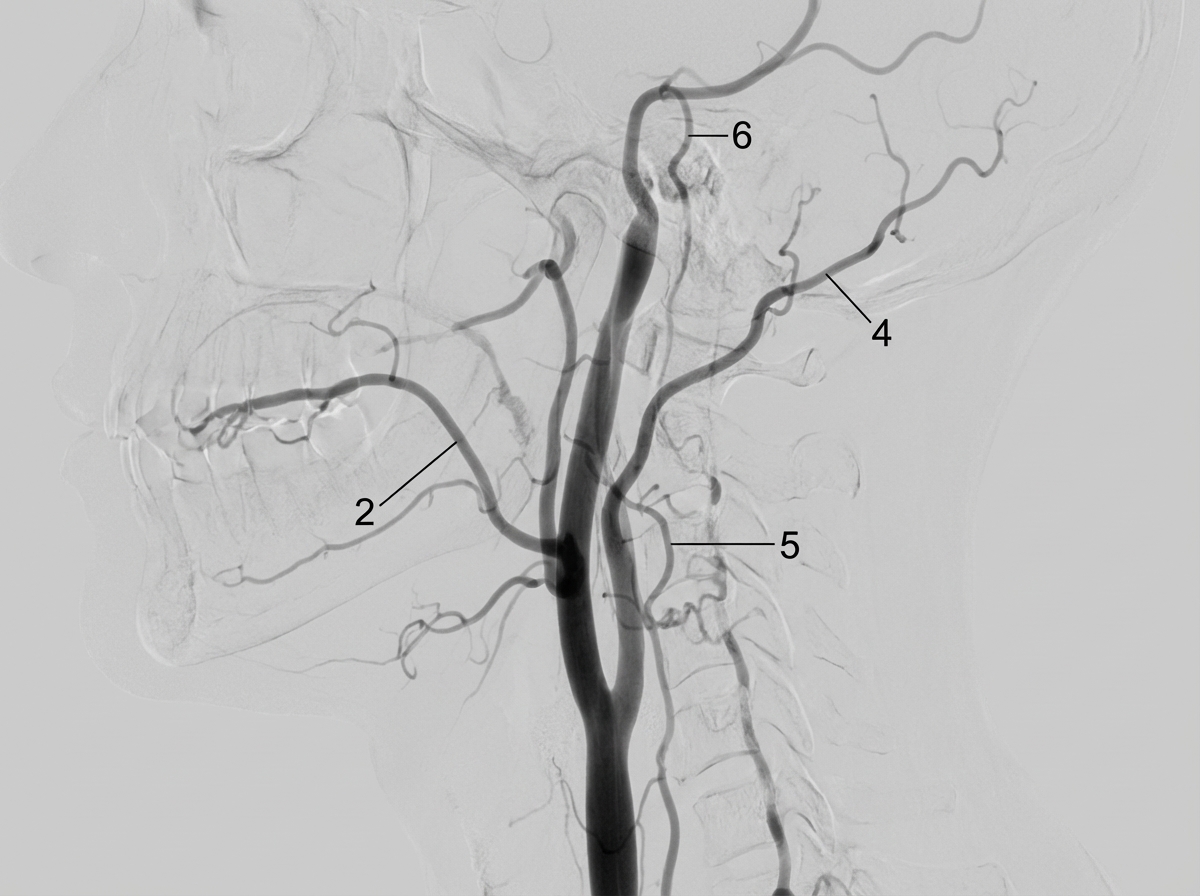

The image shows angiography of the external carotid artery. Structure labeled '5' represents:

Explanation: ***Ascending pharyngeal artery*** - The image displays an **angiography of the external carotid artery**, and structure labeled '5' clearly represents the **ascending pharyngeal artery** - This artery is typically a **slender branch arising from the medial aspect** of the external carotid artery, **ascending vertically** along the pharynx - It is the **smallest and most medial branch** of the external carotid artery *Lingual artery* - This is labeled as structure '2' in the angiography - Arises from the **anterior surface** of the external carotid artery at the level of the hyoid bone - Courses anteriorly to supply the tongue *Occipital artery* - This is labeled as structure '4' in the angiography - Arises from the **posterior aspect** of the external carotid artery - Courses posteriorly and superiorly to supply the posterior scalp *Posterior auricular artery* - This is labeled as structure '6' in the angiography - Arises from the **posterior aspect** of the external carotid artery above the occipital artery - Courses posteriorly to supply the auricle and scalp behind the ear